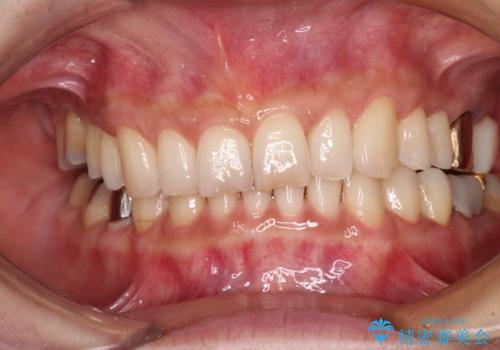

デコボコの歯とむし歯 インビザライン矯正治療とむし歯治療

- 奥歯が咬めないくらいに痛いとのことで来院された患者様です。

痛みの強い歯は、歯髄組織が強い炎症を起こしており、神経を取り除く必要であったため、速やかに根管治療を行いました。

その後、オールセラミッククラウンにて補綴治療を行う予定でしたが、処置した歯以外にも治療が必要と思われる歯があったり、デコボコした歯列も気になるとのことで、患者様希望によりインビザラインにてマウスピース矯正を行うこととしました。

まずは矯正治療前に必要なむし歯処置を行い、その後矯正治療を行ってから、最後にオールセラミッククラウンなどで補綴治療を行うこととしました。

咬合力が非常に強く、全体的に歯が擦り減っている状態であったので、理想的な咬み合わせを達成することは難しく、また咬合力が強い方のマウスピース矯正は、思い通りに動かないことがあるため、ワイヤー矯正の方が望ましいように思えました。

治療途中で2年強、体調を崩されて通院ができなくなってしまったため、必ず通院が必要なワイヤー矯正ではなく、マウスピース矯正で結果的には無事に治療を終えることができました。